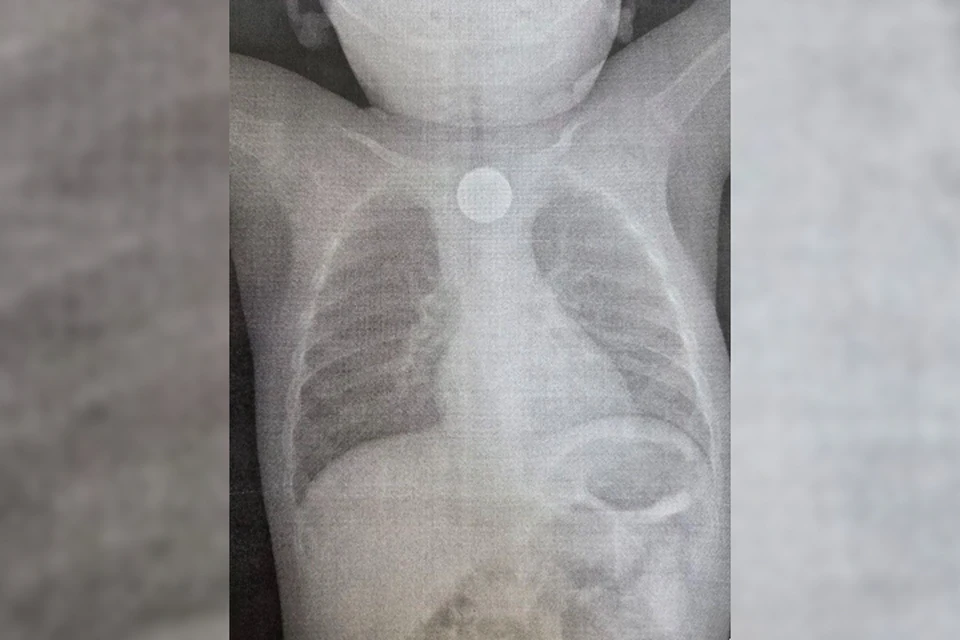

годовалый мальчик проглотил сразу два опасных предмета. Фото: ДРКБ.

В Улан-Удэ медики спасли жизнь ребенку. Повод для обращения шокировал даже опытных врачей: годовалый мальчик проглотил сразу два опасных предмета - монету и литиевую батарейку. Подробности – в материале КП-Иркутск.

- Бригада врачей во главе с эндоскопистом Зориком Хангаловым немедленно провела операцию. С помощью эндоскопа они извлекли из пищевода малыша двухрублевую монету и маленькую, но очень опасную литиевую батарейку. Именно она, вступив в реакцию со слизистой оболочкой, успела вызвать сильный химический ожог, - рассказали в пресс-службе ДРКБ.